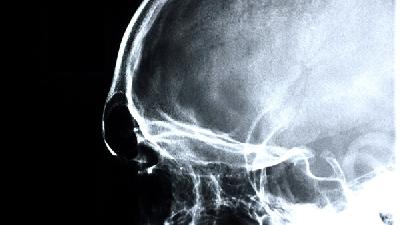

區(qū)分腦癱與發(fā)育遲緩需結(jié)合神經(jīng)影像學(xué)檢查、運(yùn)動(dòng)功能評(píng)估、發(fā)育量表測(cè)試及實(shí)驗(yàn)室檢查等綜合判斷。 1、神經(jīng)影像學(xué): 頭...